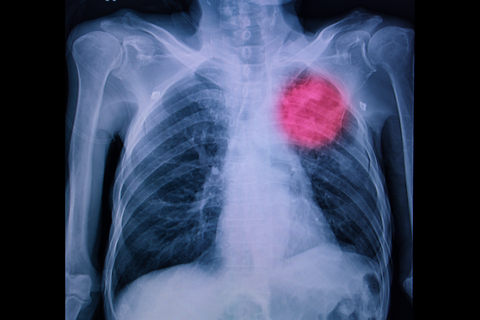

Рак лёгких - один из самых опасных видов онкологических заболеваний, который ежегодно уносит жизни миллионов людей по всему миру. Он часто диагностируется на поздних стадиях, что снижает шансы на выживание. Однако большинство случаев рака лёгких можно предотвратить, если следовать здоровому образу жизни и избегать вредных привычек.

Интересный факт: в США каждый год более 228 тысяч человек получают диагноз рака лёгких, а более 142 тысяч умирают от этой болезни. Это делает рак лёгких одним из самых распространенных и смертоносных видов онкологии в США.